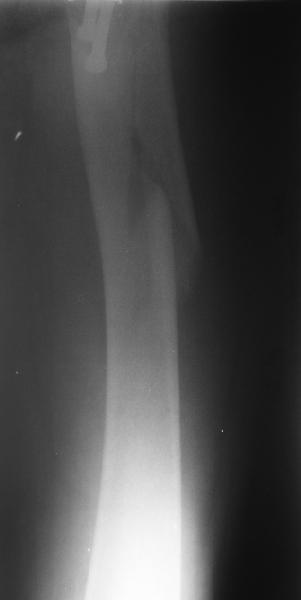

Regarding this specific patient, it is quite difficult for me to discern the exact fracture pattern and therefore treatment suggestions. It appears to be a spiral fracture starting just proximal to the less trochanter and extending distally 6 or more cm into the shaft with medial displacement of the distal fragment. The lesser troch is a seperate fragment. The 2 year old femoral neck fracture appears to have healed in good position I really can't tell where the fracture starts laterally, but presumably it's near the distal most screw.

I can't tell if there is further comminution of the shaft or the greater trochanter. I can barely see the fracture on the lateral radiograph. I'm not sure but I don't see AVN of the femoral head nor OA of the hip. Her overall bone quality appears normal for a 68 year old. I don't see any loosening of the screws but I can't tell for sure.

The fracture extention well into the shaft makes intramedullary fixation somewhat more appealing than plate fixation and contrasts with the case posted by Bill. A reconstruction nail with proximal locking into the femoral head and neck after screw removal and reduction would be reasonable.